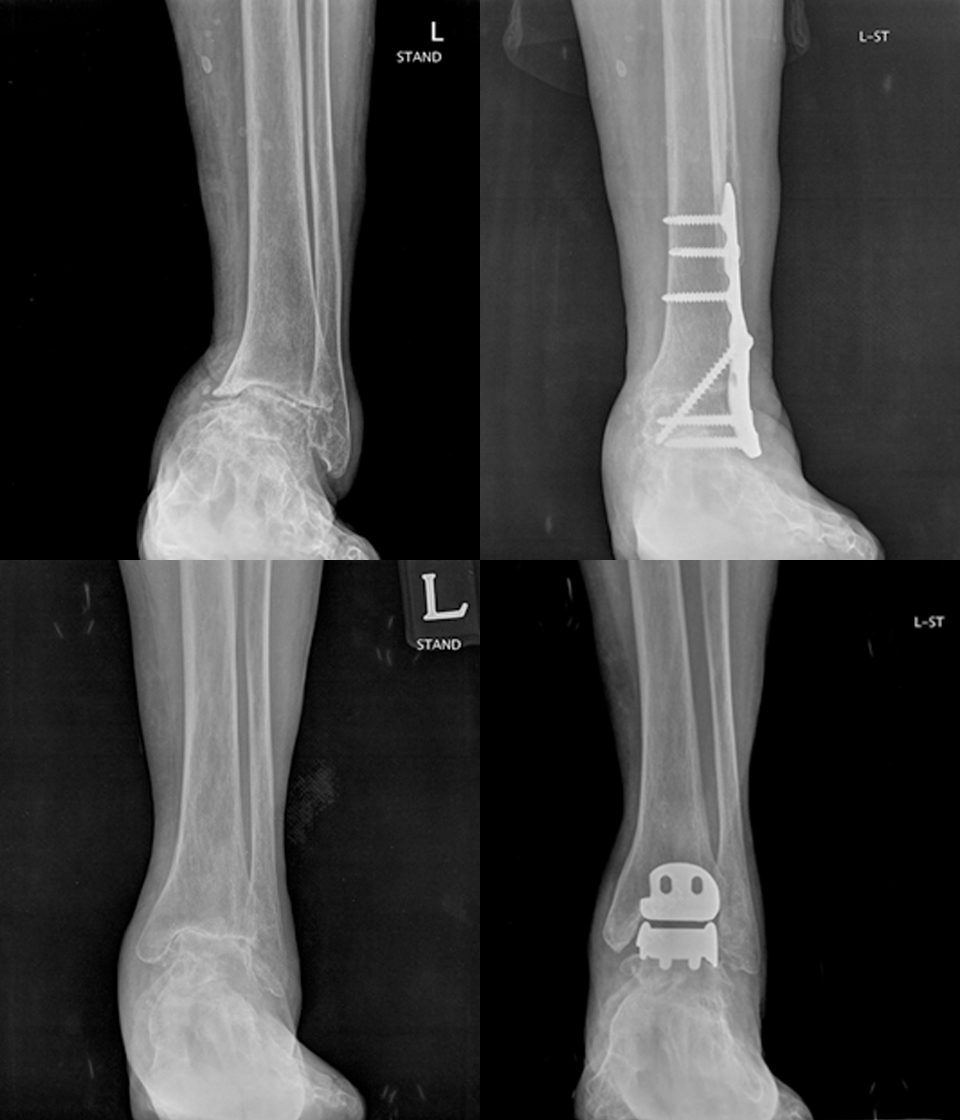

OA

족관절 관절염

족관절 관절염 이란

무릎과 마찬가지로 발목관절에도 관절염이 생기는데,

무릎과 달리 과거 외상에 의한 외상성 관절염이 많습니다.

발병원인

과거 족관절 외상(염좌 및 골절), 퇴행성 관절염, 류마티스 관절염 등

주요증상

• 발목 관절의 통증, 부종

• 운동 범위 감소, 변형

3. 수술치료

• 과상부 절골술

• 족관절 유합술

• 족관절 인공관절

- 환자 동의하에 게시된 이미지입니다.